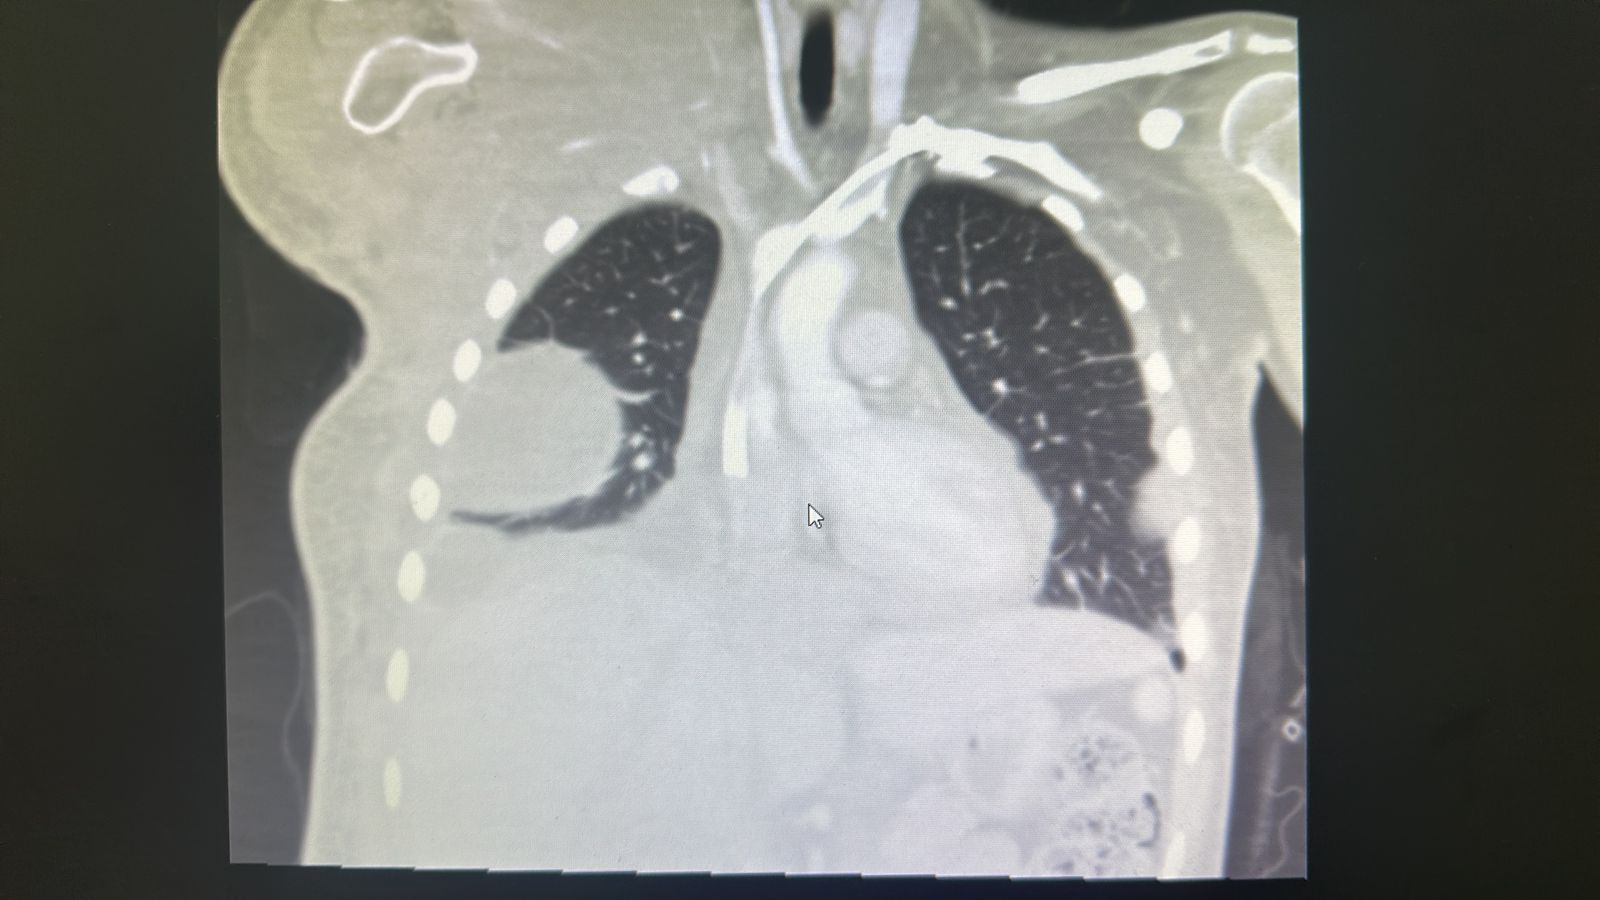

Más InformaciónLa oncología pediátrica se especializa en el diagnóstico y tratamiento del cáncer en niños. Sabemos que atravesar una enfermedad oncológica es un reto para toda la familia, por eso ofrecemos un entorno empático, seguro y acompañamiento continuo.

Contamos con procedimientos de alta complejidad para lograr un diagnóstico certero: